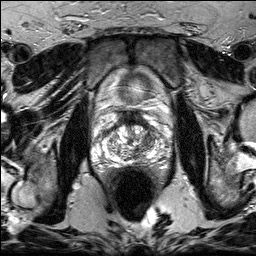

Denoising diffusion probabilistic models (DDPMs) have achieved unprecedented success in computer vision. However, they remain underutilized in medical imaging, a field crucial for disease diagnosis and treatment planning. This is primarily due to the high computational cost associated with (1) the use of large number of time steps (e.g., 1,000) in diffusion processes and (2) the increased dimensionality of medical images, which are often 3D or 4D. Training a diffusion model on medical images typically takes days to weeks, while sampling each image volume takes minutes to hours. To address this challenge, we introduce Fast-DDPM, a simple yet effective approach capable of improving training speed, sampling speed, and generation quality simultaneously. Unlike DDPM, which trains the image denoiser across 1,000 time steps, Fast-DDPM trains and samples using only 10 time steps. The key to our method lies in aligning the training and sampling procedures. We introduced two efficient noise schedulers with 10 time steps: one with uniform time step sampling and another with non-uniform sampling. We evaluated Fast-DDPM across three medical image-to-image generation tasks: multi-image super-resolution, image denoising, and image-to-image translation. Fast-DDPM outperformed DDPM and current state-of-the-art methods based on convolutional networks and generative adversarial networks in all tasks. Additionally, Fast-DDPM reduced training time by a factor of 5 and sampling time by a factor of 100 compared to DDPM. Our code is publicly available at: https://github.com/mirthAI/Fast-DDPM.